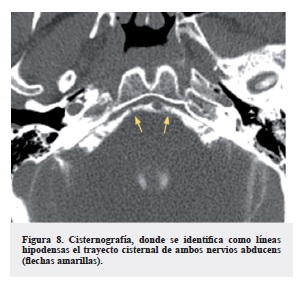

Cuando existe una lesión tumoral en la topografía de un nervio craneal, la tomografía puede ser útil para la detección de compromiso óseo, sin embargo, el reconocimiento de los nervios de pequeño tamaño como el abducens son de difícil caracterización, pues la presencia del líquido cefalorraquídeo cistenal hipodenso no proporciona un adecuado contraste con estas estructuras (Figura 7). La administración de contraste intratecal para realización de cisternografía nos puede brindar un mejor contraste y visualización (Figura 8), sin embargo, hoy en día considerado un procedimiento invasivo que no aporta información adicional en comparación a la resonancia, que ofrece mejor contraste en la caracterización de los nervios, debido a la disparidad que nos proporciona el líquido cefalorraquídeo adyacente en secuencias ponderadas en T2 (nervio isointenso rodeado de líquido hiperintenso). La RM (Figura 9 y 10) es el método de elección para evaluar los nervios craneanos, y el VI no es la excepción. Estos nervios constituyen un grupo de estructuras que han adquirido durante su desarrollo filogenético un alto grado de especialización. Hay 12 pares de nervios a los cuales nos referimos por su nombre o número correspondiente y son visibles a través de técnicas de resonancia. En la evaluación convencional del cerebro con RM pueden ser observados los nervios más grandes como el óptico, oculomotor, trigémino, facial y vestibular; sin embargo, para los otros nervios, es necesario realizar cortes finos y reconstrucciones multiplanares, así como secuencias adicionales como Fast Imaging Employing Steady State Adquisition (FIESTA) (Figura 11), Short Tau Inversion Recovery (STIR), Fluid Attenuated Inversion Recovery (FLAIR) o Cube., estas dos últimas, utilizadas sobretodo en la caracterización y extensión de algunos tumores.